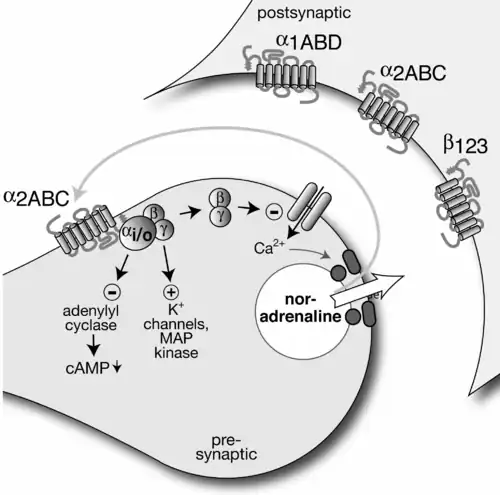

After premonitions for example in the work of the Portuguese pharmacologist Serafim Guimarães, α-adrenoceptor subclassification came in 1971 with the discovery of the self-regulation of noradrenaline release through α-adrenoceptors on noradrenergic synaptic terminals, presynaptic α-autoreceptors. Their existence was initially combated but is now established, for example by the demonstration of their messenger RNA in noradrenergic neurons.[84][85][86] They differed from α-receptors on effector cells and in 1974 became the prototype α2-receptors, the long-known smooth muscle contraction-mediating receptors becoming α1.[87]

Presynaptic α2-autoreceptor and postsynaptic adrenoceptors of a noradrenergic axon terminal.

Presynaptic α2-autoreceptor and postsynaptic adrenoceptors of a noradrenergic axon terminal. -